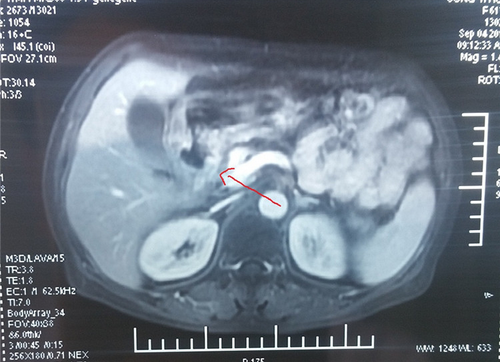

2017-07-07(治疗前)腹部强化CT:胃窦癌伴腹膜后、腹腔淋巴结转移,累及胰头,胰腺颈。

2017-09-03(治疗后)腹部MRI提示:腹腔内无淋巴结肿大。

患者2月前来的我院肿瘤科,考虑到患者年龄大,饮食少,伴有腹痛,体质差,预计生存期3月。我院肿瘤科杨金山副主任医师与中医专家田思强科主任进行中西医结合讨论,充分论证,对这种病情复杂的肿瘤晚期患者,决定采取单药口服化疗及中药调理。单药口服化疗具有副作用小的特点,结合中药扶正祛邪,调节免疫等干预。经2周期的精心治疗,2017-09-03查腹部MRI提示:腹腔内转移瘤消失,胃窦部肿瘤明显缩小。患者饮食、体力状况明显改善,腹痛缓解,能独立正常生活,患者及家属满意。中西医结合治疗凸显了在肿瘤治疗的优势。